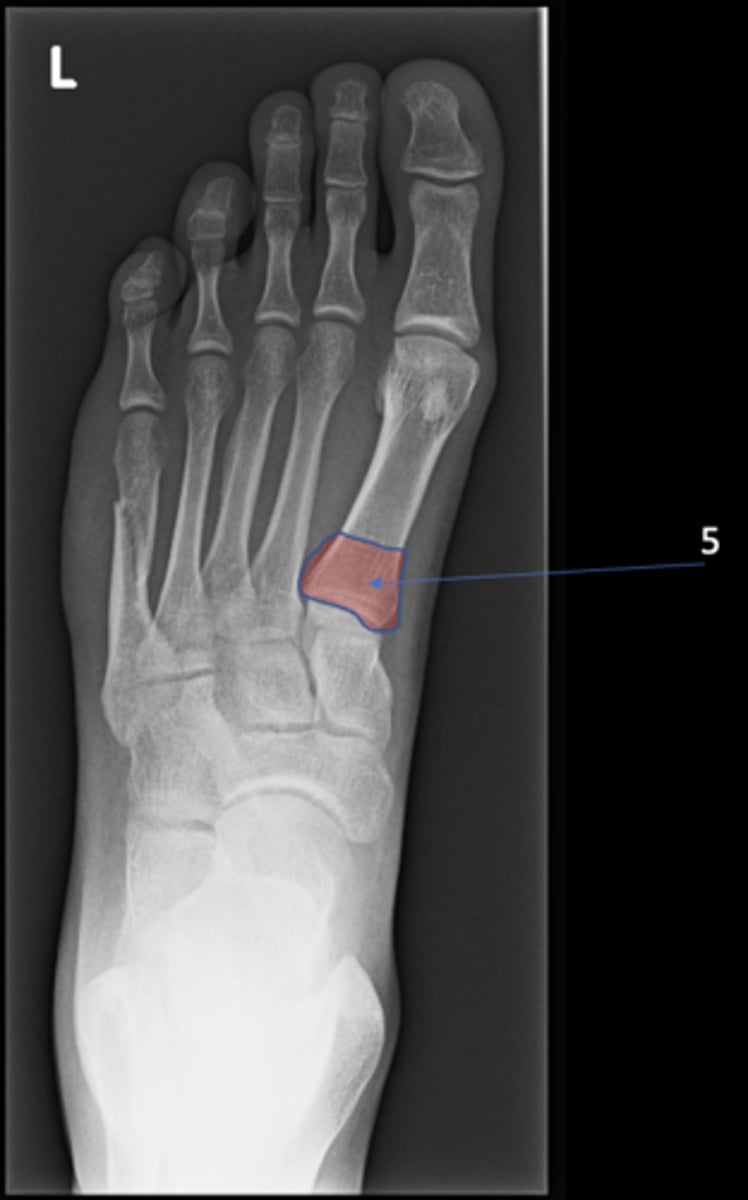

Left AP foot

View?

<p>View?</p>

91

New cards

Talus

ID 1

<p>ID 1</p>

92

Medial malleolus

ID 2

<p>ID 2</p>

93

Navicular

ID 3

<p>ID 3</p>

94

Medial cuneiform

ID 4

<p>ID 4</p>

95

Base of 1st metatarsal

ID 5

<p>ID 5</p>

96

Head of 1st metatarsal

ID 6

<p>ID 6</p>

97

Lateral sesamoid bone

ID 7

<p>ID 7</p>

98

Medial sesamoid bone

ID 8

<p>ID 8</p>

99

Cuboid

ID 9

<p>ID 9</p>

100

Base of 5th metatarsal

ID 10

<p>ID 10</p>